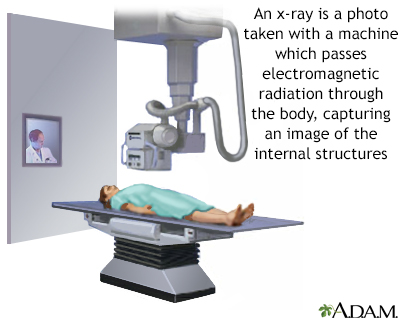

If more pressure is put on a bone than it can stand, it will split or break. A break of any size is called a fracture. If the broken bone punctures the skin, it is called an open fracture (compound fracture).